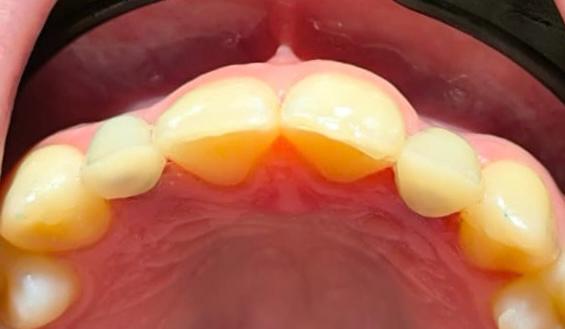

Muchos de nuestros pacientes sufren de agenesia, una condición en la que los dientes definitivos (comúnmente los laterales) nunca llegan a salir. Esto suele dejar un espacio estrecho y un hueso que, al no haber tenido nunca la raíz de un diente, es muy delgado.

En lugar de abrir grandes heridas para colocar hueso artificial, utilizamos implantes de última generación conocidos como monobloque. Estos implantes están diseñados específicamente para ser colocados en espacios muy reducidos, aprovechando hasta el último milímetro de tu hueso natural.

Para nosotros, la precisión es innegociable. Antes de empezar, analizamos tu estructura ósea con tecnología de imagen avanzada. Esto nos permite ver lo que otros no ven y planificar una cirugía que apenas deja huella en tu organismo.